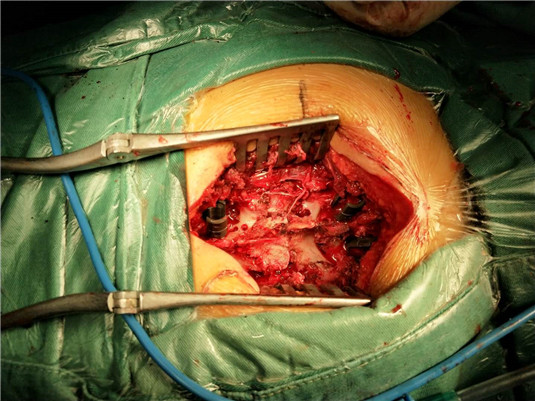

在陈月明主任亲自主刀下,装钉固定、骨折复位、脊髓松解……经过大家4个多小时的奋战,夜里近2:00手术终于顺利完成。患者入院时病情危重已经截瘫,幸运的是通过大家的努力,年轻的生命得到了延续……